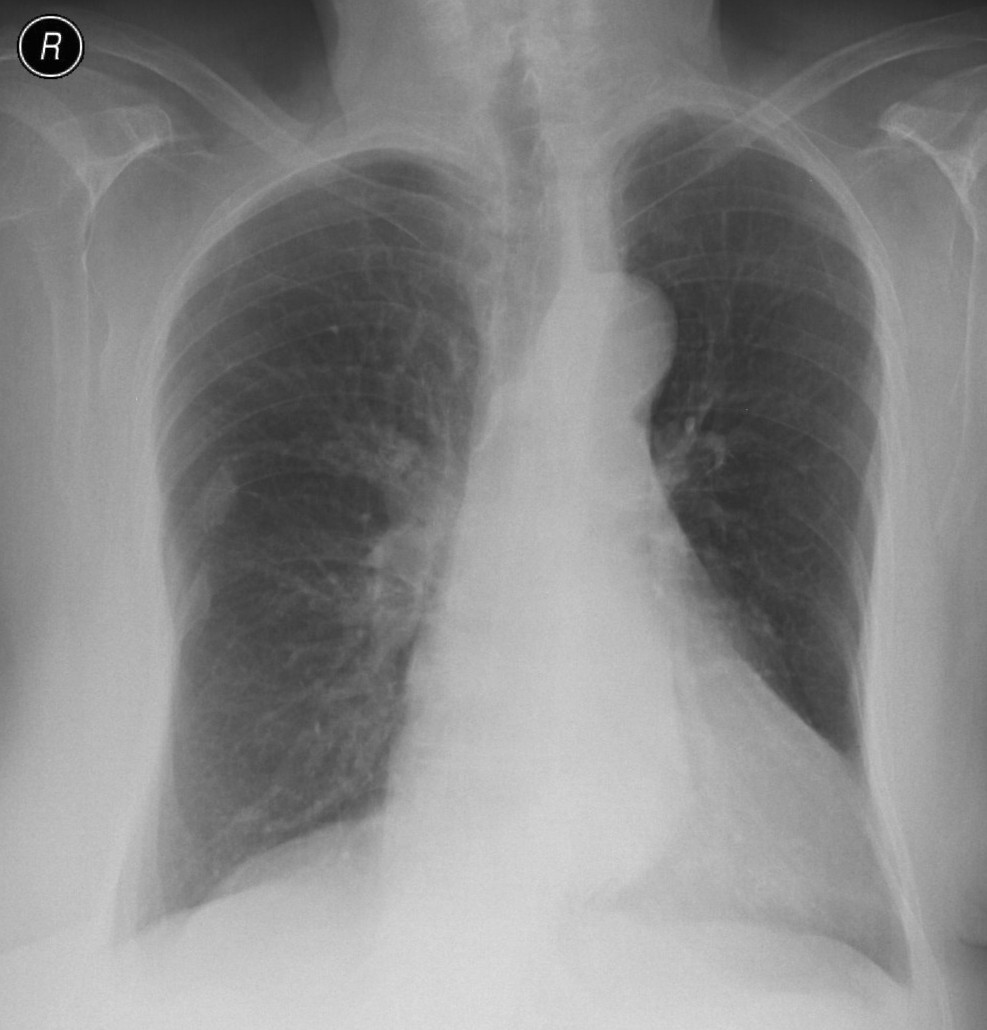

1a: Normal chest X-ray 1b: Chest HRCT examination

Image

2a: Atelectasis, PA chest radiograph.Hx of esophagus exstirpation surgery. (by the contribution of Zsuzsanna Monostori, MD, PhD) Parahilar right side hypolucency. (small amount of pleural effusion in the right lateral sinus)

2b. Atelectasis, left upper lobe. CECT, coronal reconstr. (by the contribution of Zsuzsanna Monostori, MD, PhD)